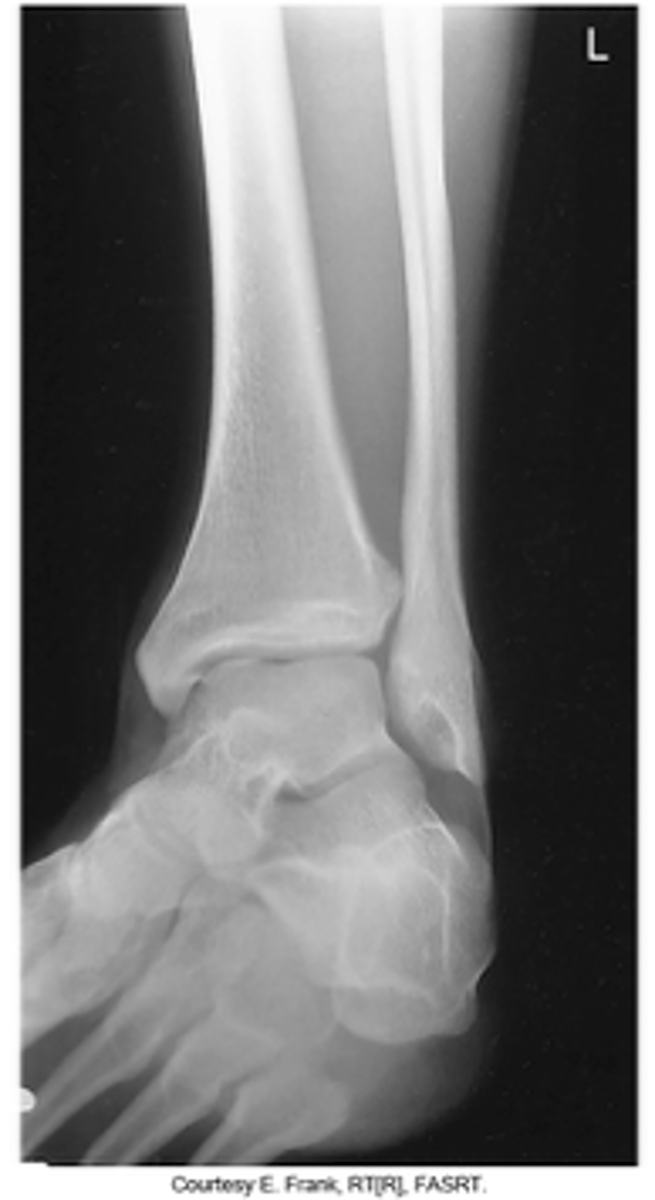

Lateral Ankle (Mediolateral)

What projection is this?

Lateral Ankle (Lateromedial)

Evaluation Criteria Lateral Ankle

- CR Centered to Medial Malleolus

- Entire talus and calcaneus visualized

- Lateral malleolus superimposed over posterior half of tibia

- Optimal exposure factors